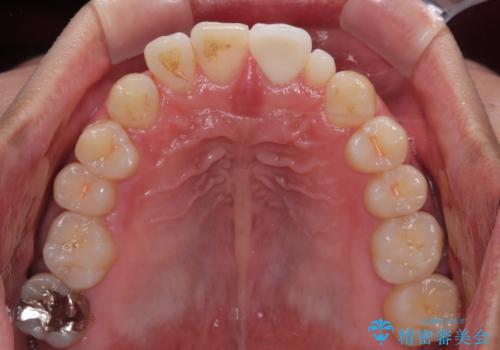

- 隙間を埋めた材料の変色や形を気にして来院された患者様です。

矯正治療などを含めて治療方法を相談した結果、当該歯をオールセラミッククラウンにて補綴治療を行うこととしました。

前歯の単独歯の補綴治療であったので、オーダーメイドタイプをおすすめしましたが、今回は既製タイプにて製作を進めました。

既製タイプでしたが、違和感のない仕上がりとなりました。